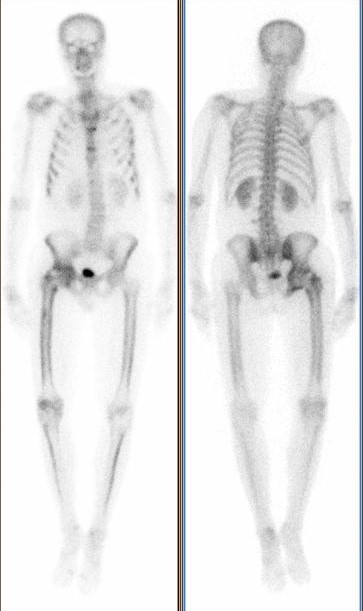

Homme de 45 ans, poly traumatisme 6 mois auparavant.

Prothèse de hanche (erreur, en réalité ostéo synthèse…) sur fracture du col fémoral.

Limitation douloureuse de la hanche

Ossifications hétérotopiques de la hanche droite (grade 3 de la classification de Brooker je dirais mais pas évident sur ces images avec artéfacts métalliques).

Séquelles de fractures multiples du gril costal et du sternum.

Hyperfixation de la corticale des membres inférieurs « en rail » pouvant faire évoquer une ostéoarthropathie hypertrophiante pneumique (syndrome de Pierre Marie et Foix).

Concernant la hanche droite, je ne vois pas de prothèse mais du matériel d’osteosynthèse, notamment une plaque vissée de reconstruction du cotyle !

Donc : arthropathie coxo-fémorale post-fracturaire sans a priori d’osteonécrose de la tête fémorale , et avec ossifications heterotopiques.

Ceci dit, bravo Trevor, il s’agit bien d’une ossification hétérotopique, brooker 2 ou 3, avec une faible activité ostéoblastique.

Je plussoie pour l’ostéomalacie qui pourrait expliquer la « belle » fixation du squelette notamment des membres inférieurs (avec une élimination urinaire qui semble relativement faible) et des fractures costales multiples passées inaperçus.

Il présente donc une ostéomalacie carentielle par malabsorption, bravo à Trevor et à Boramy!

La scintigraphie oriente vers ce diagnostic: multiples fissures costales, hyperfixation périostée avec des foyers assez ponctuels en faveur de stries de Looser-Milkman.